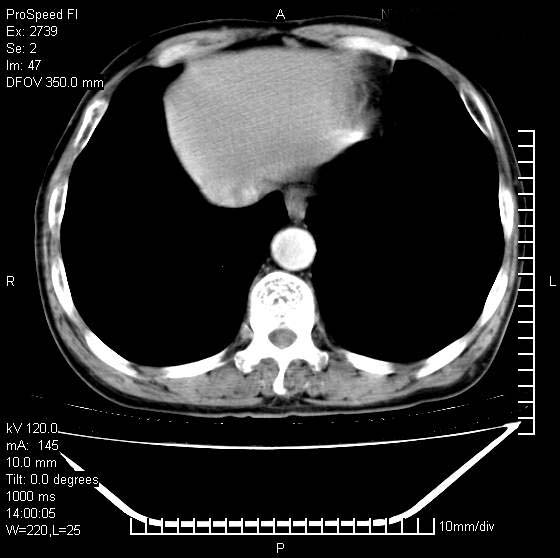

以下是引用andymaomao在2007-12-7 15:54:00的发言:[br]1.双上肺陈旧肺tb灶;[br]2.双中上肺矽肺;[br]3.双肺气肿;[br]4.图中箭头所指乃下腔静脉。

以下是引用山之魂海之韵在2007-12-7 18:59:00的发言:[br]支持矽肺,左肺上叶陈旧性结核,肺气肿。箭头所指乃下腔静脉。下腔静脉显影比主动脉显影迟,增强动脉后迟可以是不均匀的。

以下是引用chengjiaqiu1在2007-12-7 17:49:00的发言:[br]矽肺,左肺上叶陈旧性结核,肺气肿。中箭头所指乃下腔静脉。